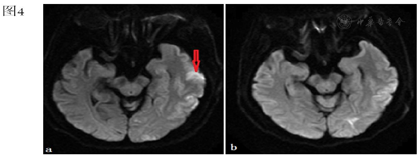

行心电图:窦性心律,T波改变;急查血常规、凝血功能、降钙素原、心肌损伤标记物、BNP未见明显异常。血气分析:酸碱度7.345,二氧化碳分压45.7 mmHg,氧分压74.4 mmHg,乳酸2.1 mmol/L;胸部CT提示:左心室腔可疑气体影(图2)。颅脑CT未见异常,急诊颅脑MRI示:左侧额颞顶枕叶、右侧额顶叶及其皮层下、左侧小脑半球多处新发脑梗死灶(图3a、图4a、图5a)。颈动脉超声:双侧颈动脉内膜增厚。患者同日转入ICU进一步治疗,入室体格检查:T 37.8℃,P 87次/分,R 15次/分,BP 190/109 mmHg,鼻导管吸氧,血氧饱和度98%。浅昏迷状态,GCS评分:E2V2M4,双侧瞳孔等大等圆,直径约2 mm,光反射迟钝。双肺听诊呼吸音清,心脏听诊律齐,未闻及杂音及额外心音。四肢肌张力增高,双侧巴氏征阳性。

本例患者,老年女性,体检发现右肺结节,为明确诊断行CT引导下肺穿刺活检术,术后出现意识改变、肌力下降、肢体抽搐等症状,胸部CT示左心室腔可疑气体影;颅脑MRI示多发新鲜脑梗。双侧颈动脉超声未见狭窄或斑块,既往无房颤病史,暂不支持脑栓塞及脑血栓形成。结合患者穿刺后出现症状、体征及影像学检查,科室内共同讨论后,考虑空气栓塞导致脑梗死不除外。